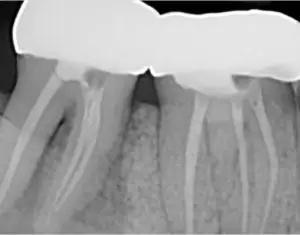

Another dentist referred a patient to me. While the dentist did a great job on the patient’s root canal, the patient was still experiencing pain.

John West, DDS, MSD, explains the important role that 3-D CBCT technology can play in benefitting both the clinician and the endodontic patient in this